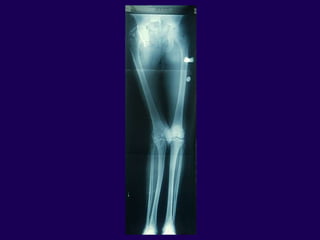

Fractures After TKA

Neer Classification of Supracondylar

Fractures

l Type I - Minimal displacement

l Type IIA - Medial displacement of

condyles

l Type IIB - Lateral displacement

of condyles

l Type III - Supracondylar and shaft